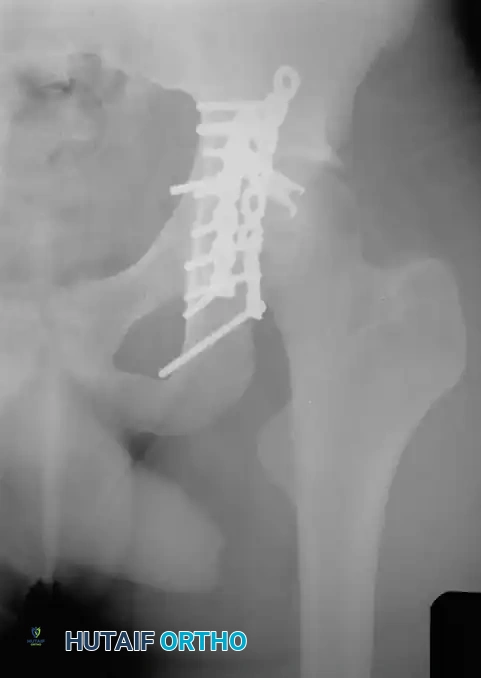

Fig. 53-4 Anteroposterior pelvic radiograph ( A ) and CT scan ( B ) of irreducible hip dislocation with posterior wall acetabular fracture. Posterior wall fragment is incarcerated, blocking reduction.

If closed reduction under conscious sedation or general anesthesia fails, urgent open reduction is mandated. A rapid, fine-cut (2-3 mm) Computed Tomography (CT) scan should be obtained to identify the incarcerating fragment—often a rotated posterior wall fragment or an intra-articular osteochondral loose body. Prolonged dislocation exponentially increases the risk of femoral head osteonecrosis and irreversible sciatic nerve ischemia.

Associated Surgical & Radiographic Imaging

Hutaifortho's Orthopaedic Diagram